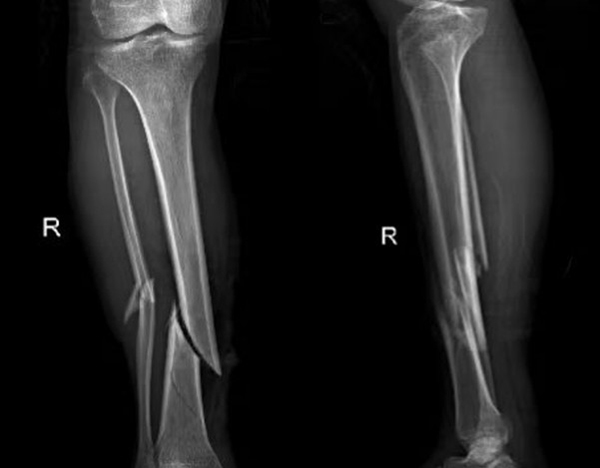

比如外傷患者,排查有無四肢骨折,X光片是首選,因為它能快速清晰顯示骨骼的連續(xù)性;而檢查關節(jié)內(nèi)的軟組織(如韌帶、半月板),則需要靠MRI,CT對此幾乎“無能為力”。所以,別主動要求“升級”檢查,聽從醫(yī)生的專業(yè)建議,才能既準確又高效。